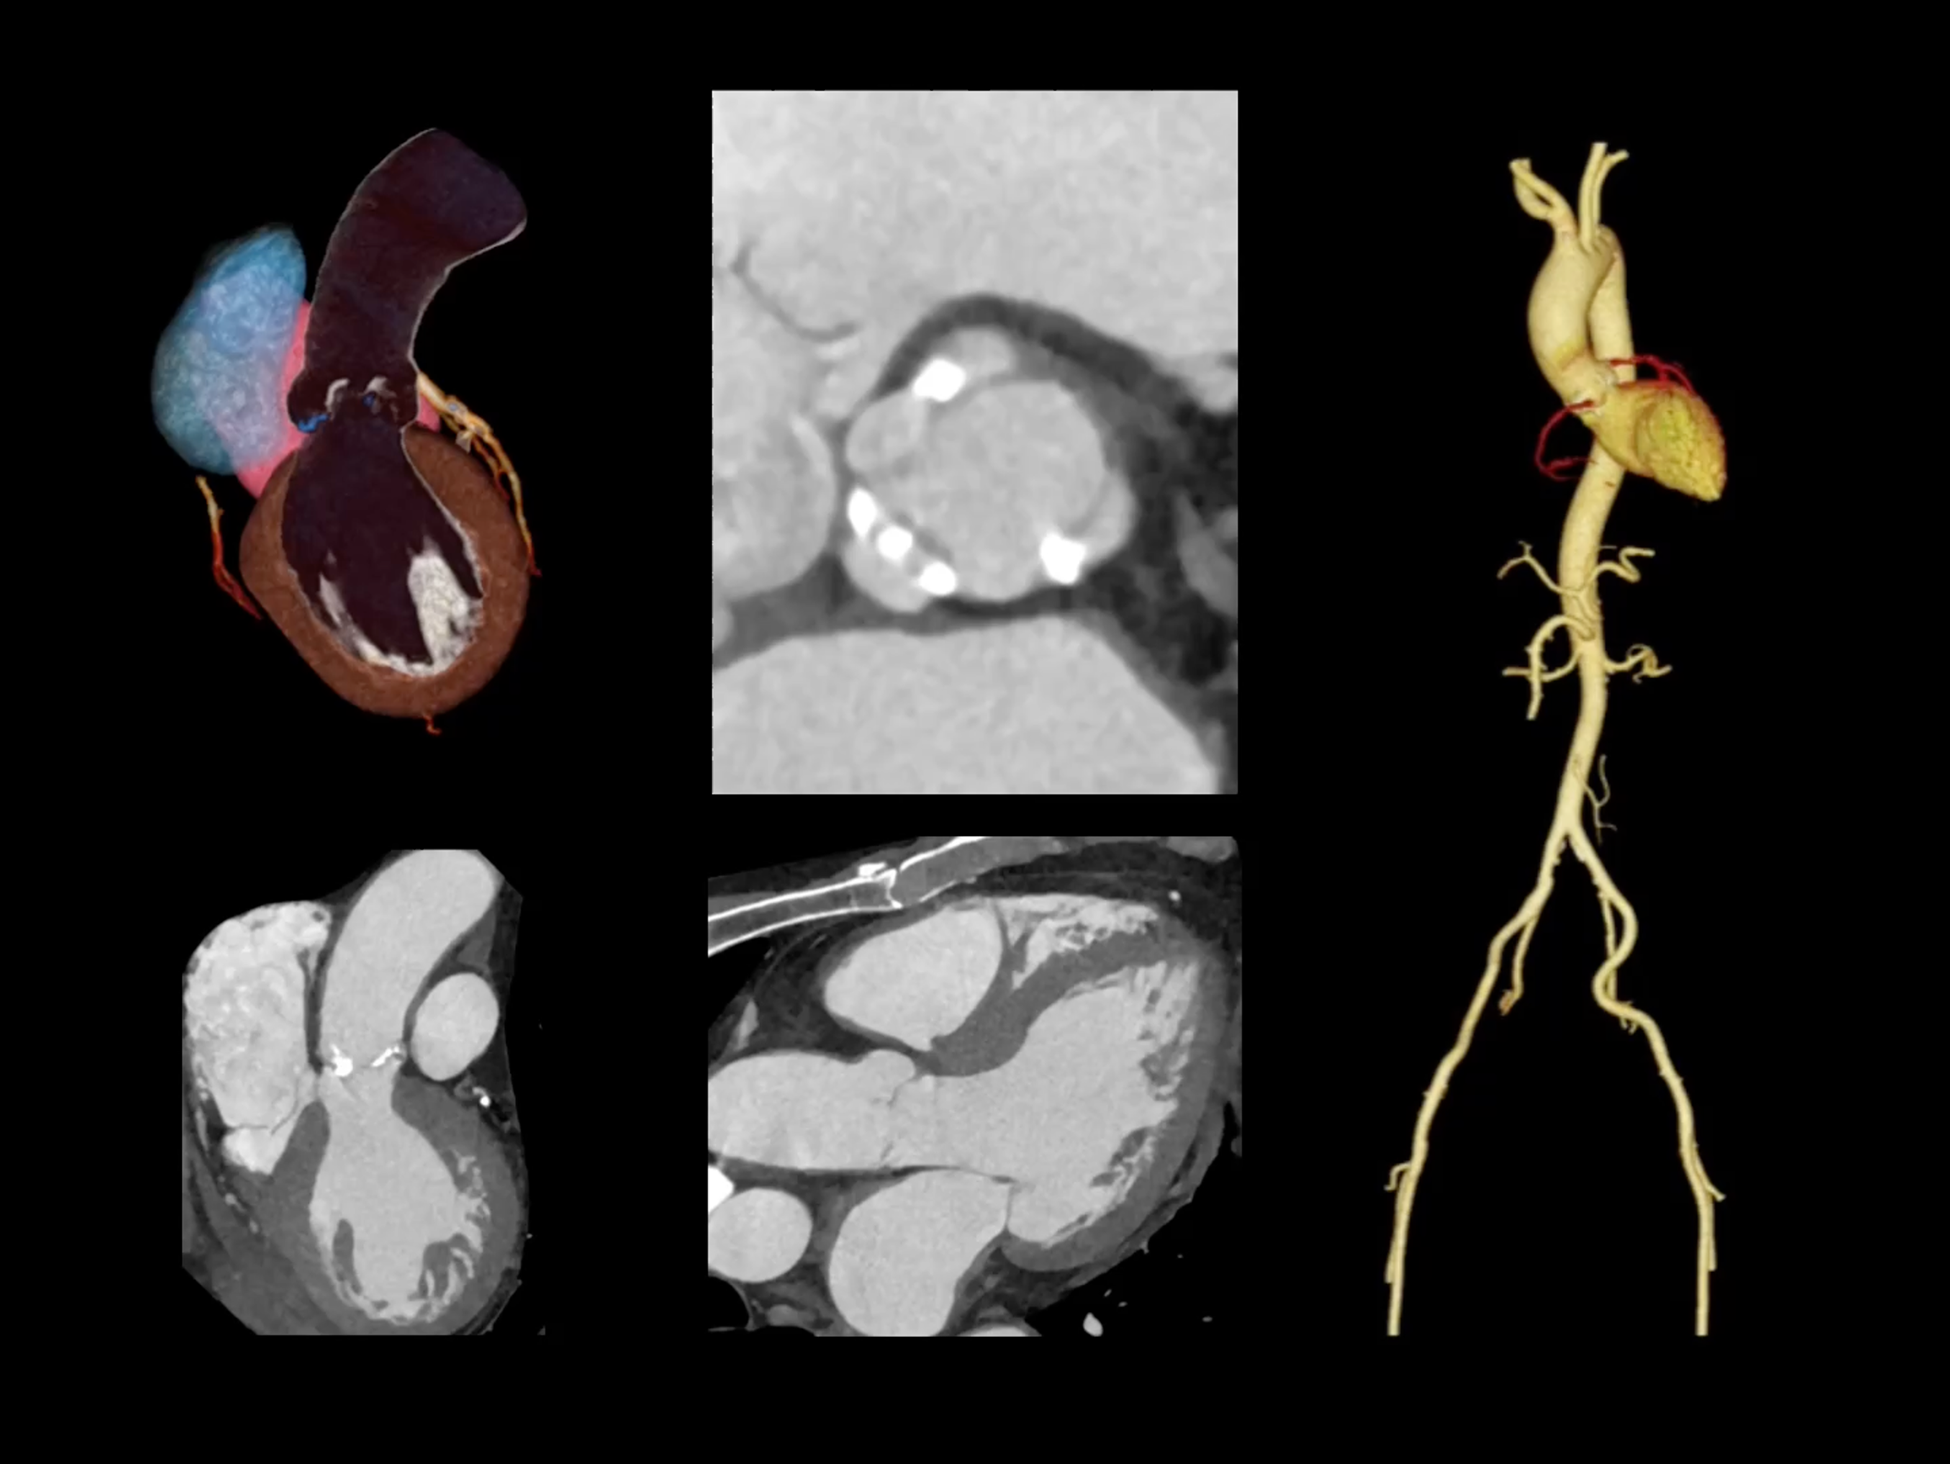

全域能谱

uCT SiriuX® 依托16cm超宽探测器与双源能谱技术,实现真正意义上的全身高清能谱成像。单次扫描同步获取灌注、能谱等多维定量参数,精准解析组织特性与病灶成分,为临床决策提供更深层次的诊断依据。

全身高清能谱成像

uCT SiriuX® 采用独有的双宽体探测器设计,实现470mm超大视野与全脏器容积覆盖的能谱成像,轻松应对不同体型患者和扫描部位应用需求。配合创新能谱重建影像链与精准双能数据配准,系统可有效抑制伪影、提升信噪比,在全脏器范围内提供高质量能谱图像,显著拓展临床精准诊断的广度与深度。

能谱成像可揭示丰富的物质与能量信息,其临床价值的充分释放有赖于完善高效的后处理分析平台。uCT SiriuX® 提供全面能谱高级分析工具,覆盖心血管、肿瘤、神经、骨科等多类临床场景。平台支持动脉增强分数分析(AEF)、细胞外容积分析(ECV)、肿瘤同源性分析、肺栓塞分析、骨髓水肿分析等多项评估,并提供多达10种基物质对成像,为精准诊断与科研探索提供坚实支撑。